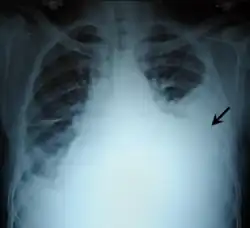

Chest X-ray showing left sided hemothorax (arrowed)

Chest X-ray

Two chest X-rays: left showing a massive left-sided hemothorax; right showing a massive right hemothorax

A chest X-ray is the most common technique used to diagnosis a hemothorax.[23] X-rays should ideally be taken in an upright position (an erect chest X-ray), but may be performed with the person lying on their back (supine) if an erect chest X-ray is not feasible. On an erect chest X-ray, a hemothorax is suggested by blunting of the costophrenic angle or partial or complete opacification of the affected half of the thorax. On a supine film the blood tends to layer in the pleural space, but can be appreciated as a haziness of one half of the thorax relative to the other.[5] A small hemothorax may be missed on a chest X-ray as several hundred milliliters of blood can be hidden by the diaphragm and abdominal viscera on an erect film. Supine X-rays are even less sensitive and as much as one liter of blood can be missed on a supine film.[24]